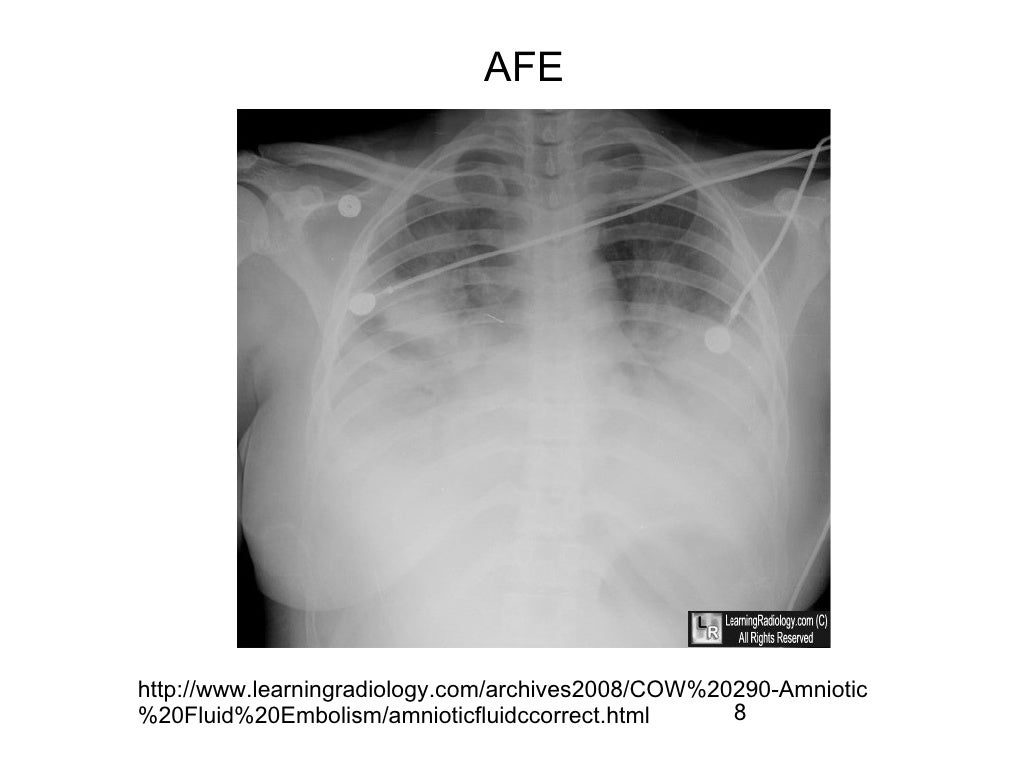

Flitzpatrick KE, van den Akker T, Bloemenkamp KWM, et al. Amniotic fluid embolism incidence, risk factors and outcomes: A review and recommendations. Ces astuces visent à fournir aux cliniciens de l’information qui pourrait améliorer leur capacité à poser un diagnostic en temps opportun et à assurer un traitement de soutien approprié aux patientes atteintes d’une embolie amniotique.ġ. Dans cet article, nous présentons cinq énoncés clés qui portent sur les facteurs de risque, le tableau clinique et la prise en charge de l’embolie amniotique dans un contexte clinique. Malgré la rareté de cette affection, la morbidité et la mortalité maternelles et périnatales sont importantes, même dans les cas où le traitement est idéal. L’embolie amniotique est un événement catastrophique d’apparition soudaine qui doit être détecté immédiatement. The purpose of these tips is to provide clinicians with information that may improve their ability to make a timely diagnosis and establish appropriate supportive treatment to patients suffering from AFE. In this article, we present five key statements covering the risk factors, clinical presentation, and management of AFE in a clinical setting. Despite the rarity of this condition, both maternal and perinatal morbidity and mortality are significant with AFE, even in cases ideally managed. Amniotic fluid embolism (AFE) is a catastrophic, sudden-onset event that must be recognized immediately.